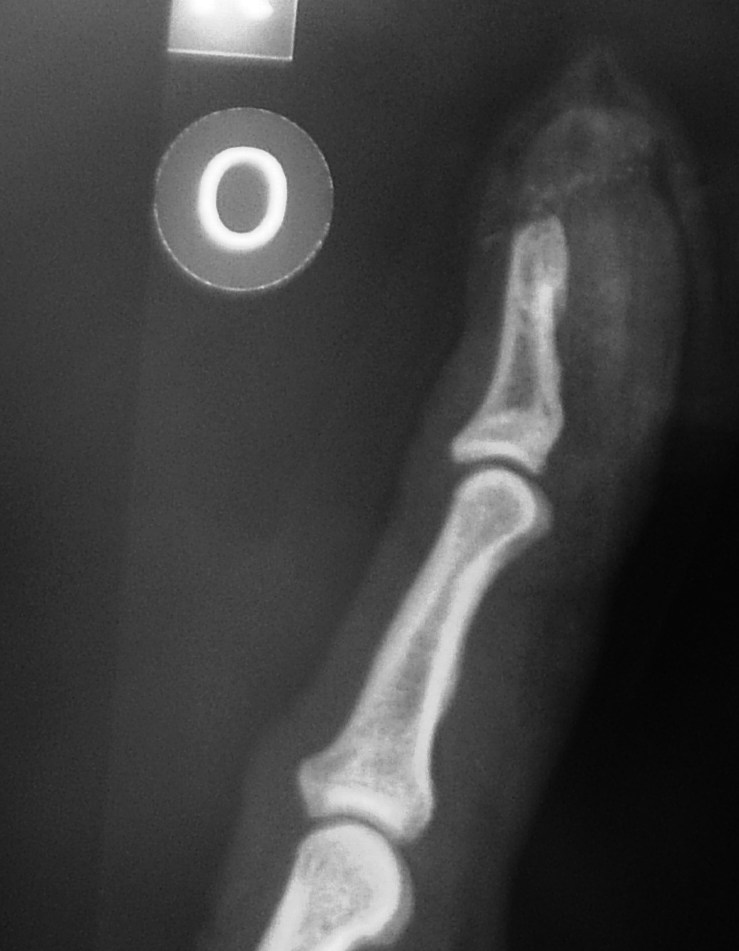

I see from the xray that you swallowed your wedding ring to stop the paramedics pinching it lol

lol, yes took us a long time to work that out... its the zipper on my cycling top... despite being plastic it sems to be opaque to xrays